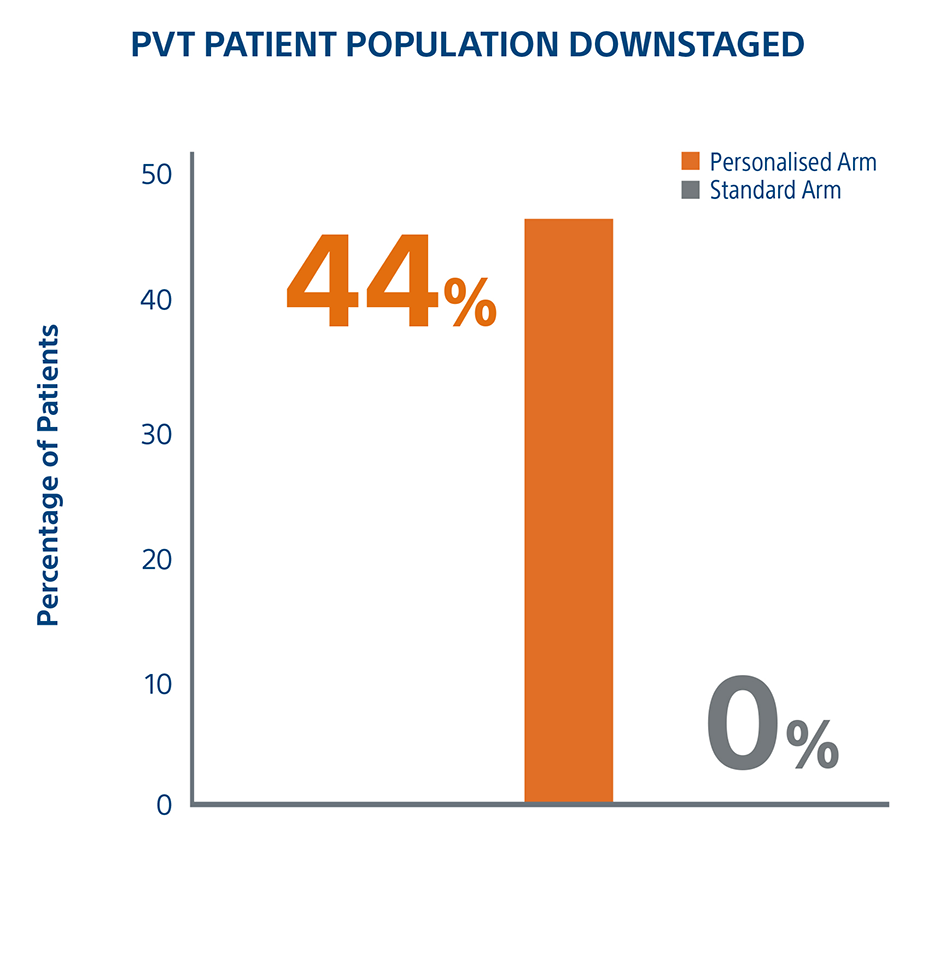

Personalized Dosimetry Downstages More Patients To Surgery